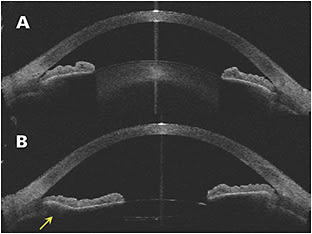

Dynamic gonioscopy allows practitioners to see structures more clearly and make the diagnosis. For example, the appositional angles of PACS deepen with dynamic gonioscopy, whereas closed angles do not deepen. Baseline measurements of the angles are obtained, which allow for grading of angle closure. Anterior-segment optical coherence tomography (OCT) or ultrasound biomicroscopy can provide further clarification if the anatomy is uncertain.8 In the author’s experience, anterior-segment OCT is also a helpful tool for explaining to skeptical patients with asymptomatic PACS or PAC that they do have a problem that requires treatment (Figure 1).

Endocyclophotocoagulation has 2 beneficial effects: (1) it ablates the ciliary epithelium and can decrease aqueous production, thereby decreasing IOP; and (2) it shrinks the ciliary processes, causing the peripheral iris to rotate posteriorly and mechanically open the anterior-chamber angle (termed endocycloplasty) (Figure 2).20-23